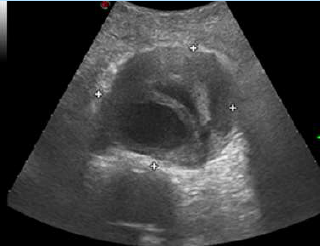

Exploración física: Palidez, sudoración profusa. Tensión arterial 60/45 mmHg, frecuencia cardiaca 140 lpm, saturación 90%, glucemia 104, Afebril. Glasgow 12. Ausculatación normal. Se evita palpación abdominal por sospecha vascular. Se realiza ecografía clínica a pie de cama objetivándose dilatación aneurismática mayor de 5 cm, con imagen hiperecogénica periférica compatible con trombo mural organizado, y luz central anecoica, flujo residual.